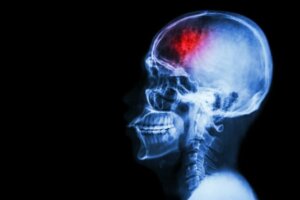

Een beroerte treedt op wanneer de bloedtoevoer naar een deel van de hersenen ontoereikend wordt of wordt afgesneden. Als gevolg daarvan kunnen neuronen beschadigd raken of zelfs afsterven. Om dit te voorkomen, zijn hier enkele maatregelen om het risico op een beroerte te verminderen.

Een beroerte is een cerebrovasculaire aandoening die de bloedvaten aantast die de hersenen van bloed voorzien. Een beroerte treedt op wanneer een bloedvat breekt of verstopt raakt door een stolsel of een ander deeltje.

Zoals in een artikel in het MSD-handboek wordt beschreven, krijgt een deel van de hersenen als gevolg van deze breuk of verstopping niet de bloed-, zuurstof- en glucosestroom die het nodig heeft. Het gevolg is dat de zenuwcellen in het aangetaste hersengebied geen zuurstof krijgen. Daardoor kunnen ze niet functioneren en sterven ze binnen een paar minuten.